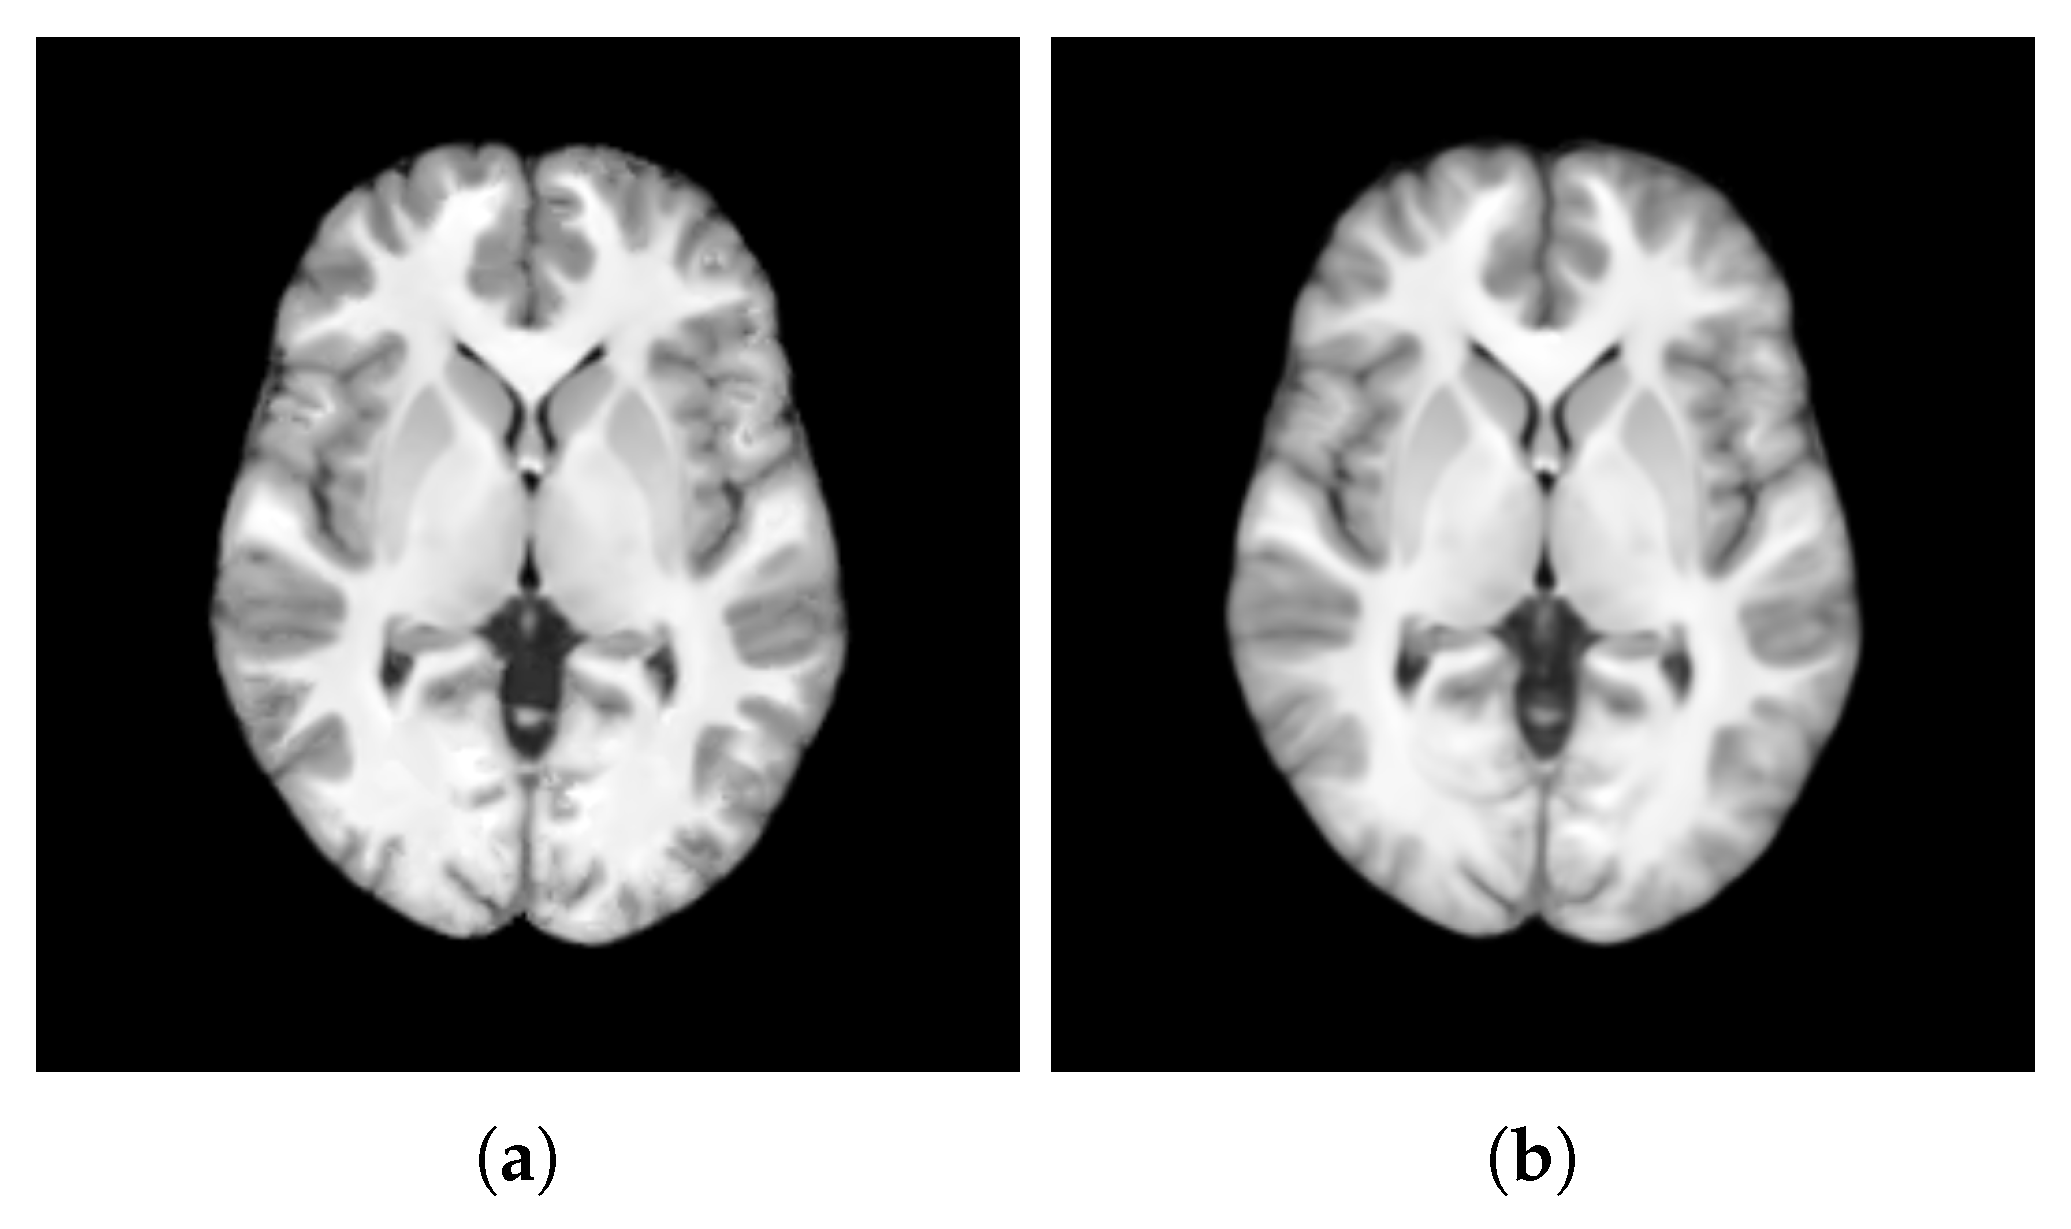

- SharpnessFigure 14 visualizes the gradient magnitude for and , with their corresponding values summarized in Table 4. The value for (60.958) was higher than that of (55.175). The higher value for indicates that the patch-based approach resulted in a template with sharper edges compared with the voxel-based averaging method. This finding suggests that patch-based estimation of template intensity can lead to sharper templates compared with traditional voxel-based averaging.

- ContrastTable 4 presents the values calculated for the pure WM and GM regions of the templates generated using the patch-based () and voxel-based () methods. Figure 15 visualizes these pure tissue regions in both templates. As shown in the table, the value for (0.418) is higher than that of (0.393), indicating higher contrast in the former. This suggests that the patch-based approach yields a template with enhanced contrast between these tissues compared with the voxel-based averaging method.